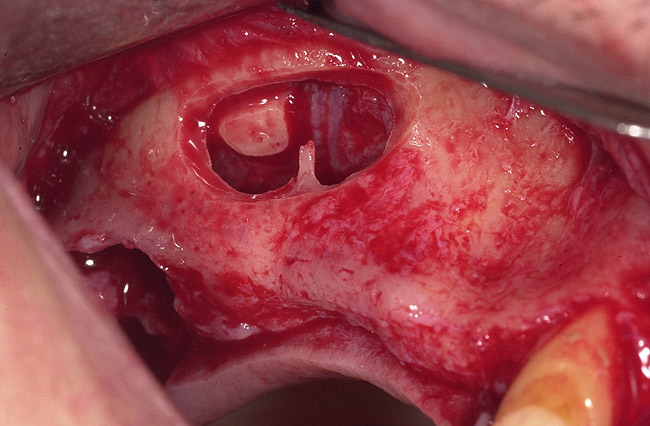

Figure 1  Buccal and radiographic views of posterior edentulism with significant sinus pneumatization in the molar region.

Figure 1

Figure 2  Buccal and radiographic views of posterior edentulism with significant sinus pneumatization in the molar region.

Figure 2